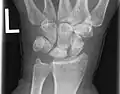

Left hand x-ray with Kienbock's Disease